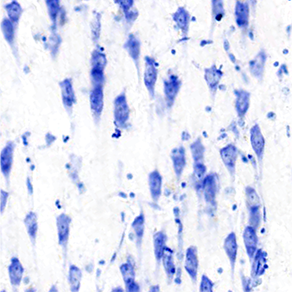

Microscopic view of hippocampal subfields [Williams et al., 2023]

Within neuroanatomy, many subregions within the hippocampus have disputed boundaries, discrepancies, and omissions. It is crucial to establish regimented protocols and remove the subjective aspect for parcellation of anatomical areas and subfields, bringing scientific rigor to the field of neuroanatomy. Aging and Alzheimer’s disease differentially affect the hippocampal subfields and thus establishing cell-validated definitions for the hippocampal subfields are needed to corroborate and determine reliable biomarkers in Alzheimer’s disease vulnerability. We have previously published a comprehensive guide to parcellating the hippocampal subfields, standardizing the parcellation characteristics. We also evaluated features assessing the hippocampal subfield prosubiculum and neighboring subfields.